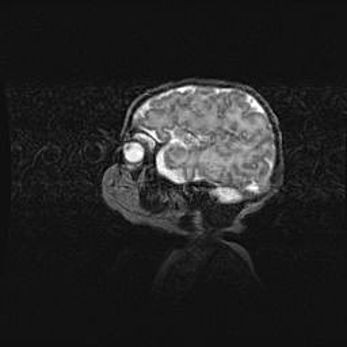

Сообщающаяся гидроцефалия. Кистозная энцефаломаляция головного мозга.

Возраст: 3 месяца 4 дня

Вес: 3100 г

Пол: женский

Окружность головы: 34 см

Срок гестации: 31 неделя

Кистозная энцефаломаляция головного мозга - одна из форм поражения головного мозга в детском возрасте. Характеризуется возникновением множественных и распространённых кист в коре, белом веществе и подкорковых образованиях головного мозга у плодов, новорождённых и детей раннего возраста. Развитие кистозной энцефаломаляции связано с внутриутробной асфиксией и гипотонией, родовой травмой, тромбозом синусов, пороками развития сосудов, инфекциями, сепсисом и другими причинами. Наиболее значимые инфекционные агенты: вирусы простого герпеса, цитомегалии, краснухи, токсоплазмы, энтеробактерии, золотистый стафилококк и другие.